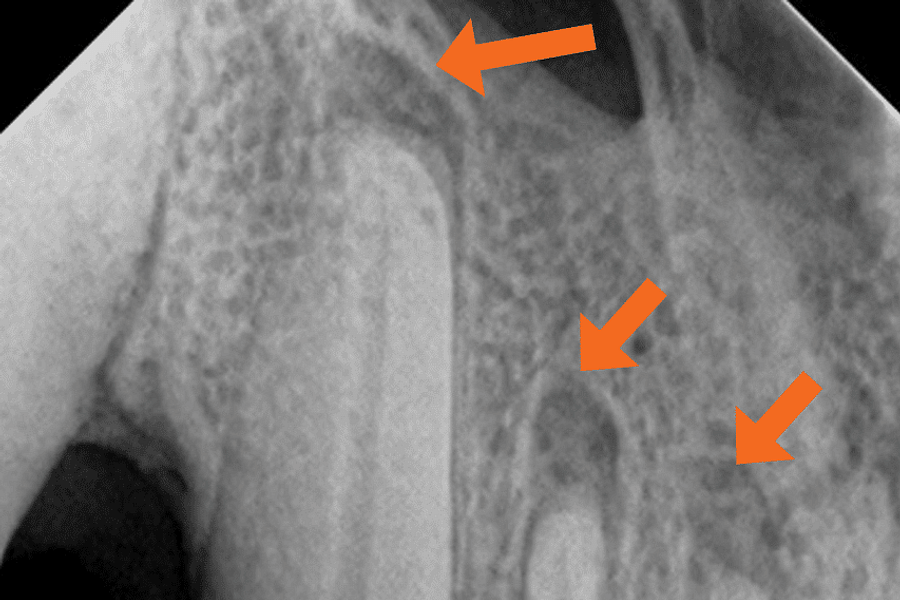

Dental X-rays are more than just tools for diagnosing cavities; they provide a comprehensive view of your oral health status. By allowing dentists to detect problems before they become severe, these images can save patients time, money, and discomfort in the long run. Early detection through modern imaging technology can reveal hidden decay between teeth, bone loss due to gum disease, or even cysts and tumors that are not visible during a standard exam.

Despite the myths surrounding dental x-rays, they play an integral role in preventative dentistry. X-rays allow dentists to detect issues that are not visible during a standard oral exam. This includes early signs of decay between teeth, problems below the gum line, and changes in bone density that could indicate periodontal disease. By identifying these problems early, fundamental dental treatments can be administered promptly, saving patients from more extensive and costly procedures down the line.